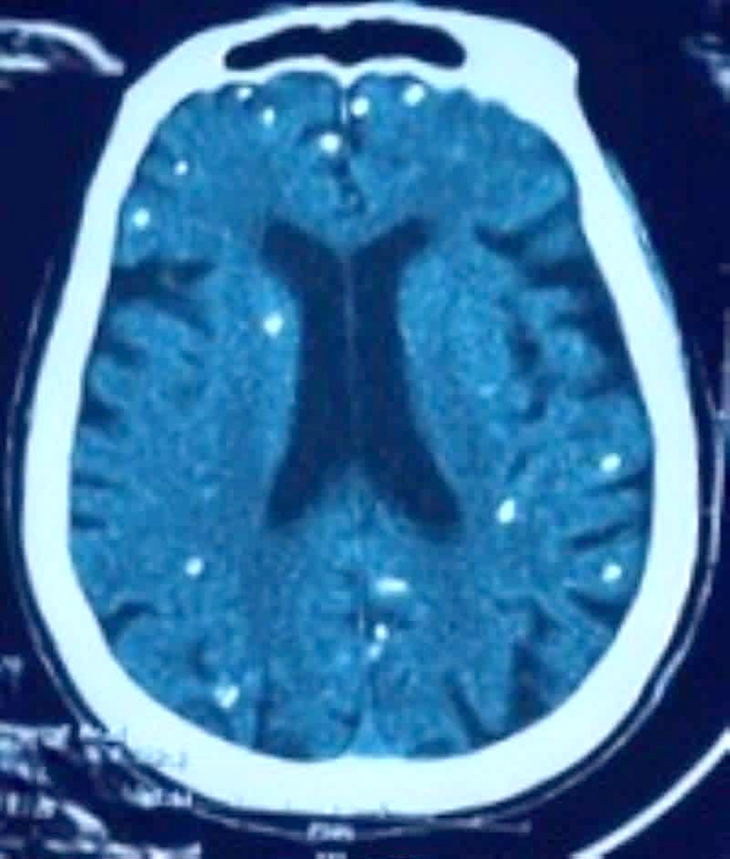

Người bệnh được chẩn đoán nhiễm ấu trùng sán dây lợn. Hình ảnh cắt lớp vi tính sọ não và X-quang ngực cho thấy rất nhiều nốt cản quang trong nhu mô não và dưới da vùng ngực - bụng.

Còn người bệnh nam ở Bệnh viện Nhân dân 115 (TP.HCM), kết quả chụp cộng hưởng từ (MRI) sọ não ghi nhận tổn thương não nhiều vị trí, phù não. Xét nghiệm huyết thanh học xác nhận kết quả dương tính với ấu trùng sán dây lợn.

Chụp X-quang xương đùi, CT-scan ngực tầm soát tổn thương ở cơ quan khác thì phát hiện vô số nang sán dải còn sống hoặc đã bị hóa vôi "ẩn nấp" trong não, nhu mô phổi và trong da, cơ trên toàn bộ cơ thể.